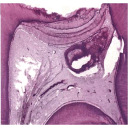

dentinareparativa.png